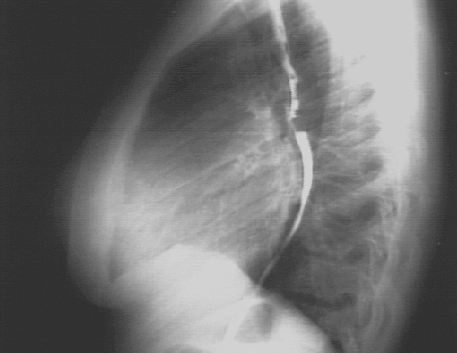

Lateral

The lateral view with barium swallow, demonstrates posterior displacement of the esophagus by the markedly enlarged left atrium.